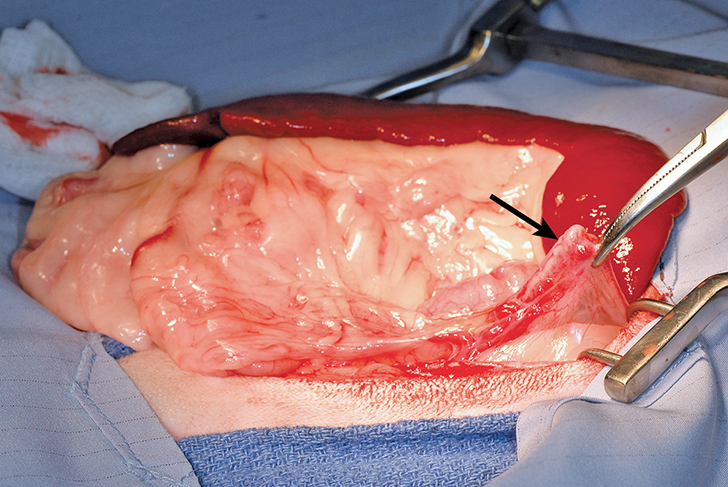

Surgical-site infections and other serious wound complications that are suggestive of infection (eg, wound pain and swelling, dehiscence, drainage; Figure 1) have been reported in 0.1% to 3% of elective gonadectomies.1,2,4,13 This rate is similar to the infection rates reported for clean, elective procedures in general (2.3%-5.7%).14 Infection rates can be reduced by decreasing surgery duration and using appropriate surgical technique (eg, gentle tissue handling, closure of dead space).14,15

FIGURE 1

Incisional infection and dehiscence after OHE in a dog (patient orientation, head left)